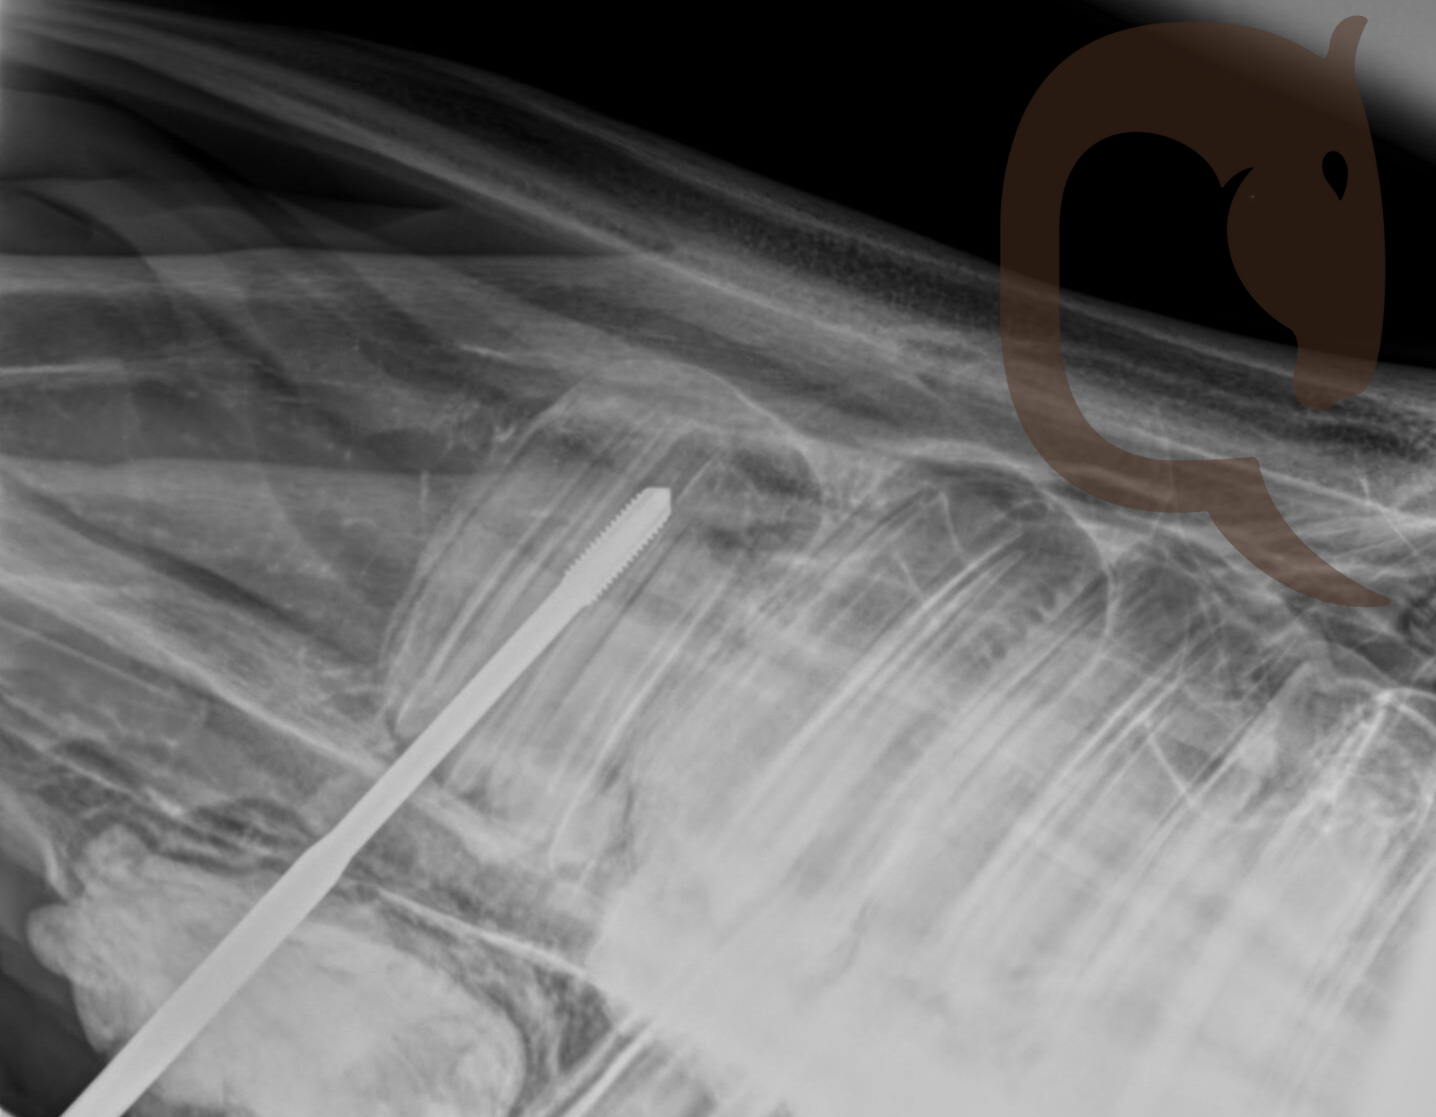

Het mondonderzoek toonde de aanwezigheid van wolfstanden 105 en 205 en dat alle doppen nog aanwezig waren. Een röntgenfoto liet zien dat tand 106 was gedraaid, met de wortel zijwaarts naar de zijkant van het hoofd gericht, terwijl tand 206 ook was gedraaid, met de wortel horizontaal naar de rostrale zijde van het hoofd gericht.

Het onderzoek concludeerde dat de gedraaide tanden verder zouden groeien, met risico op het veroorzaken van oronasale of extra-orale fistels. De aanbevolen behandeling was een chirurgische extractie via buccotomie of met een Steinman-pin.